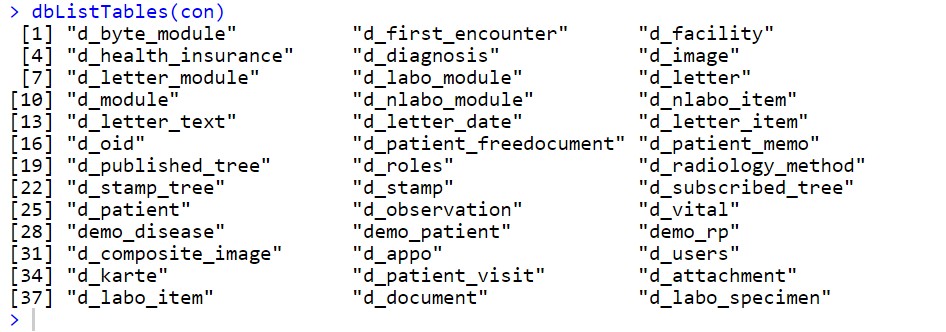

dbListTables(con)

dbDisconnect(con)dbConnectで接続オブジェクトを作って、dbListTablesでテーブルを確認したり

dbListFieldsでカラムを見たり

dbReadTableでテーブルを読み込んだり

ORCAから患者登録をして、OpenDolphinでカルテに書き込んで、Rstudioで実際にデータベースを確認してみると、いろいろアイデアが浮かんでくるかと思います。